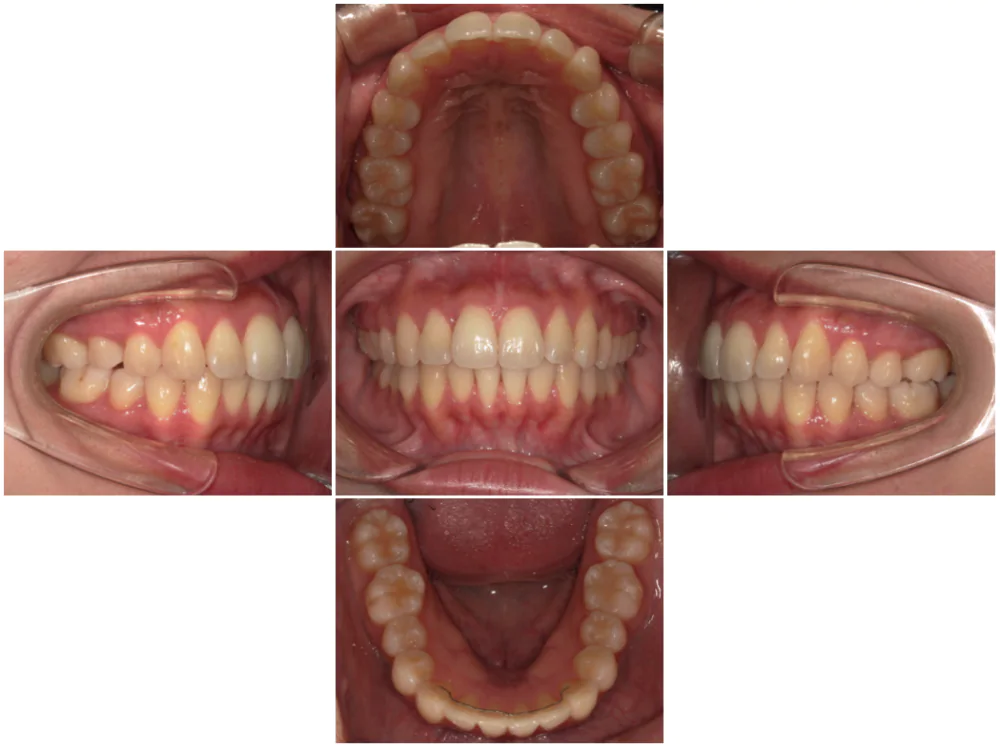

症例1

| 来院時の主訴 |

全体的なガタガタを治したい。

できれば抜歯はしたくない。

歯並びを気にせず笑えるようになりたい。

| 医院での対応や適用装置 | マウスピース矯正装置を使用して主訴であるガタガタを改善しました。 ガタガタの改善に必要なスペースの確保のために上あごの親知らずのみ抜歯を行いました。 |

| 通院期間 | 1年1ヶ月 |

| 通院回数 | 7回(治療中) |

| 治療費用総額 | 725,000円(税込) |

| リスクと副作用 | 矯正治療による歯の移動に伴う痛み、歯根吸収、虫歯 |